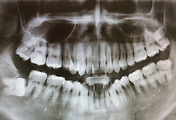

의사와 수술 날짜 잡고 집에 가려고 나왔는데, 이것저것 검사해야 된단다. ㅜㅜ 먼저 피 뽑고, X레이 찍고, 심전도 검사하고, 직장내시경 했다. 다른 거야 무난하지만 직장내시경은 하기 전에 좌약 넣고 배변을 본 후에 받아야 한다. 간호사가 좌약 넣어 주는데 항문은 외부에서 건드리거나 뮈가 들어오면 금새 배변감이 든다는 사실을 알게 되었다. 좌약 넣고 5분간 참으라는데, 3분 정도 되면 신호가 온다. 하지만 불굴의 의지로 6분을 참았다. ㅋ